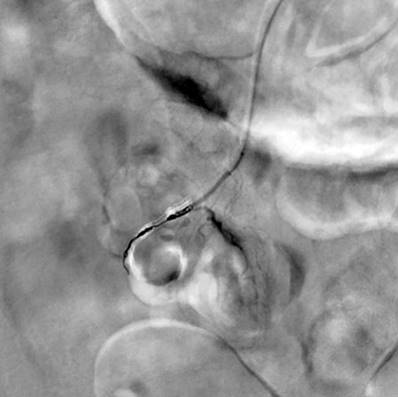

Durante los tres primeros días de hospitalización persistió con hematoquecia, hipotensión y anemización grave que no corrigió a pesar de ser politransfundido, por lo que se solicitó arteriografía mesentérica, en la cual no se encontraron lesiones que explicaran el sangrado. El paciente se tornó inestable hemodinámicamente, por lo que fue trasladado a la unidad de cuidados intensivos (UCI) con requerimiento transfusional, soporte vasopresor y ventilación mecánica invasiva. Además, tenía un cuadro de hematemesis con necesidad de endoscopia de vías digestivas altas que reportó una “angiodisplasia de bulbo duodenal, la cual recibió escleroterapia”. Por la persistencia de inestabilidad hemodinámica, sangrado digestivo bajo y anemización grave, se realizó una angiotomografía abdominal, en la que se observó una “dilatación en el segmento intestinal delgado ileal, que podría corresponder a un divertículo de Meckel, con extravasación del medio de contraste a través de este segmento” (Figura 1), por lo que se le realizó una embolización selectiva por medio de arteriografía (Figuras 2 y 3).

Figura 1 Tomografía axial computarizada, se observa una estructura quística de la pared fina con un nivel hidroaéreo correspondiente con un divertículo yeyunal. Fuente: Servicio Radiología, Hospital Comuneros. Seleccionada por autores.